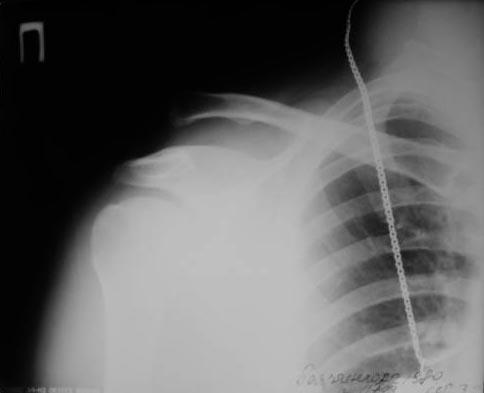

А зачем фиксировать по Веберу, если можно двумя винтами чрескожно.

В начале использовали канюлированные, а затем обычные (канюлированные жалко). Фото в приложении. Операция под ЭОПом.

Травма свежая.

Вы всегда выполняется такую гиперкоррекцию как представлено на рентгенограммах?

5. Насчет гиперкоррекции- согласен. В данном случае немного перестарался. На функциональный результат никак не повлияло. Пациент выписан к труду.